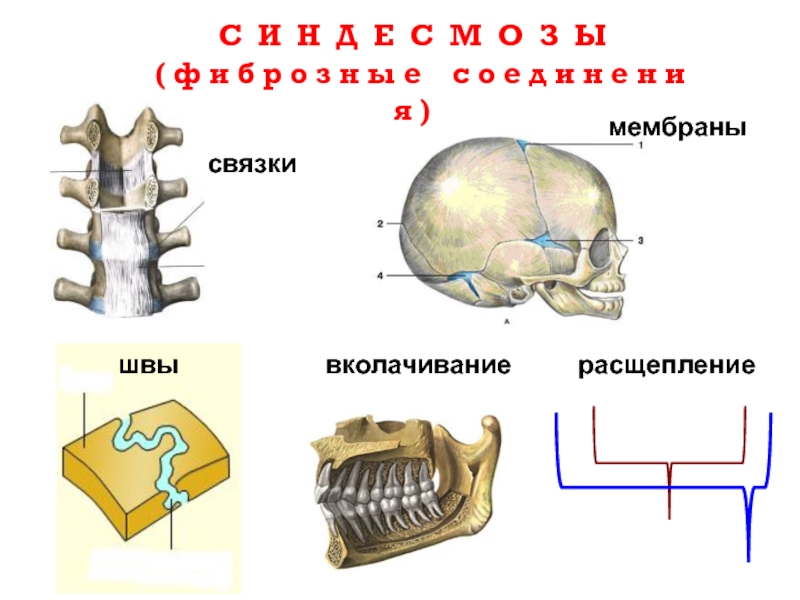

Структура и анатомия синдесмоза: научные иллюстрации